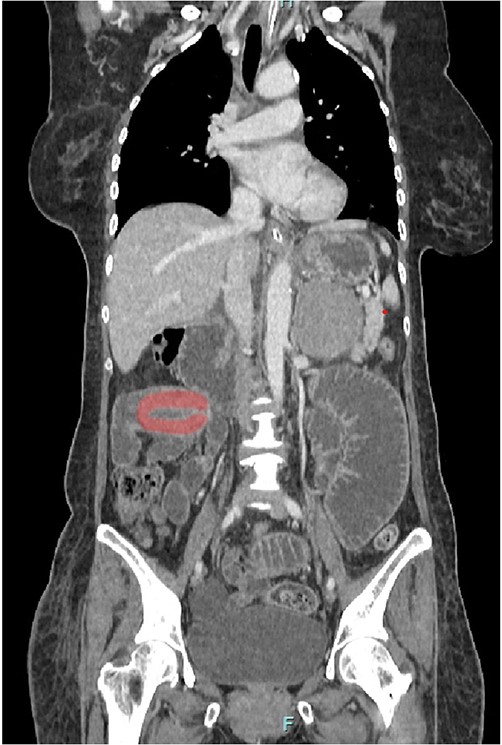

Her abdominal x-ray showed a dilated small bowel with a most likely transition point at the ileum and a collapsed large bowel (Fig. 1). Computed tomography (CT) of the abdomen showed an intussusception with the transition point at the proximal ileum with mesenteric invagination (Figs. 2 and 3).

Sagittal view of CT scan. The involved bowel loops are thickened with mesenteric invagination into the intussusception. The distal small and large bowel appears collapsed.

Coronal view of CT scan. Intussusception transition point is seen likely at the proximal ileum with evidence of ‘bowel in bowel’ appearance, measuring ~7.8 cm.